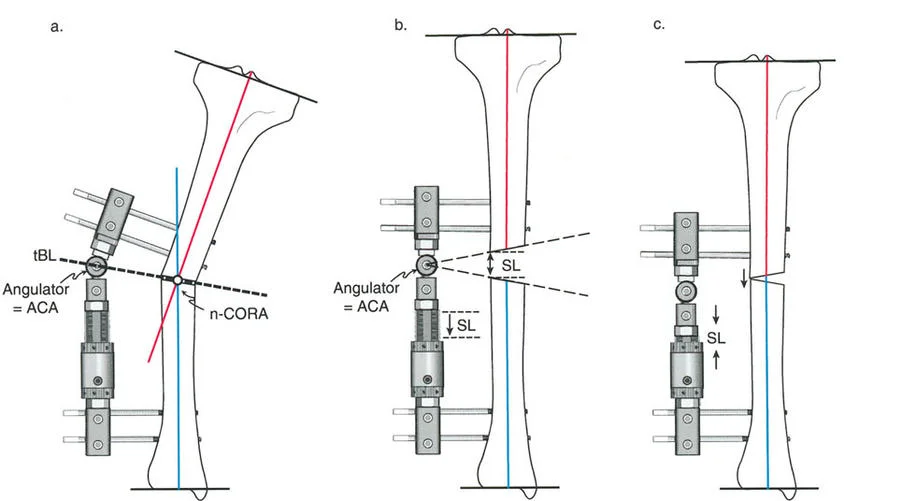

قواعد بالي لقطع العظم (Osteotomy Rules) في وضع الأجهزة

فهم قواعد بالي لقطع العظم أمر لا غنى عنه لتخطيط الإطار:

- قاعدة قطع العظم 1: عندما يمر قطع العظم ومحور تصحيح الانحراف (ACA) كلاهما عبر مركز دوران الانحراف (CORA)، فإن نهايات العظم ستنحرف دون ترجمة (انزياح). يتم استعادة المحور الميكانيكي، وتظل نهايات العظم متقاربة تمامًا، مما يخلق تصحيحًا كلاسيكيًا "إسفينيًا مفتوحًا" أو "إسفينيًا مغلقًا".

- قاعدة قطع العظم 2: عندما يمر محور تصحيح الانحراف (ACA) عبر مركز دوران الانحراف (CORA)، ولكن يتم إجراء قطع العظم على مستوى مختلف (غالبًا بسبب ضعف جودة العظم عند CORA أو مشاكل في الجلد)، فإن نهايات العظم ستنحرف وتخضع لترجمة محسوبة ومقصودة لإعادة محاذاة المحور الميكانيكي.

- قاعدة قطع العظم 3: (للاكمال) عندما يمر قطع العظم عبر مركز دوران الانحراف (CORA)، ولكن يتم وضع محور تصحيح الانحراف (ACA) خارج CORA، سيتم إنشاء تشوه ترجمة جديد، وهو خطأ شائع في وضع المفصلات غير المخطط له جيدًا.

في المنشآت القريبة من المفصل، غالبًا ما نعتمد على قاعدة قطع العظم 2. نظرًا لأنه لا يمكننا قطع العظم بأمان عند خط المفصل تمامًا (مركز دوران الانحراف CORA)، فإننا نقطع العظم في مستوى أدنى في منطقة الميتافيسيس. بعد تحقيق التصحيح الزاوي عبر المفصلات (محور تصحيح الانحراف ACA)، يتم إعادة محاذاة خطوط المحور الميكانيكي بشكل مثالي، ولكن نهايات العظم في موقع قطع العظم تتحرك بالنسبة لبعضها البعض.

معدل 1 ملم/يوم ينطبق بشكل صارم على القشرة المقعرة للعظم في موقع قطع العظم (الحافة الأمامية للإسفين المفتوح). نظرًا لأن الجهاز (قضيب الشد أو دعامة TSF) يقع على مسافة من العظم، خارج غلاف الأنسجة الرخوة، فإنه يتحرك على طول قوس أكبر بكثير. إذا وجهت المريض لشد القضيب بمعدل 1 ملم يوميًا، فإن العظم الفعلي سيُشد بجزء ضئيل من هذا المعدل، مما يؤدي إلى التصلب المبكر لموقع قطع العظم.

حساب معدل الشد الحقيقي

لحساب المعدل الصحيح للشد عند المفصلة، نستخدم قاعدة المثلثات المتشابهة، والتي تعتمد أساسًا على القاعدة الهندسية للدوائر متحدة